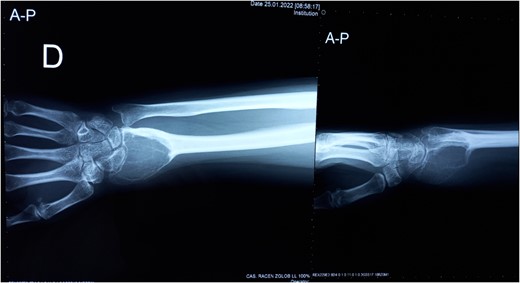

Resection of the tumor and harvesting of the bone graft from the ipsilateral proximal fibula was done simultaneously. We harvested a graft with a length of 8 cm with an inferior lateral geniculate branch and peroneal vessels to be used in the reconstruction of the defect that remained after the resection of the tumor (Fig. 2). After placing the graft in the place of the defect, the inferior lateral geniculate branch was anastomosed through a terminal-lateral anastomosis with the radial artery, while the vein was connected to the cephalic vein through an end-to-end anastomosis. The graft was fixed with a plate and screws, and two Kirschner wires (Fig. 3).

Reconstruction of the defect after resection of the GCTB of the distal radius and anastomosis of the vessels.